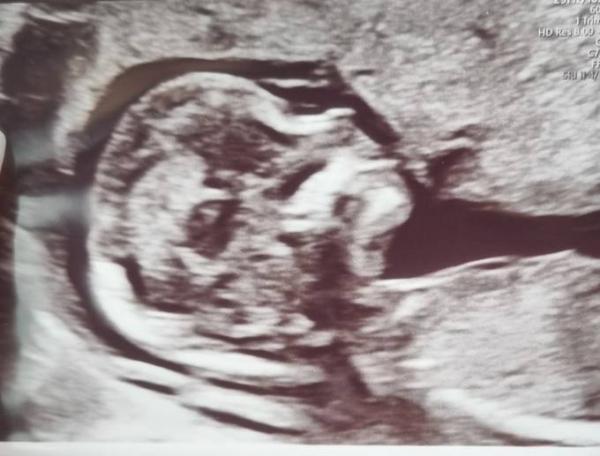

Guten Morgen, ich war gestern zum Ersttrimester-Screening. Ab morgen rutsche ich schon in die 15. SSW- Wahnsinn wie die Zeit rennt. Wir haben gestern einen Umschlag mit dem Geschlecht erhalten, das Geheimnis enthüllen wir in 2-3 Wochen; wenn wir auch die Ergebnisse vom NIPT Bluttest mit Geschlechtsbestimmung haben. Ich bin schon soo gespannt. Wie geht es euch aktuell?

Bild zu Ersttrimester-Screening - Forum für November - Mamis